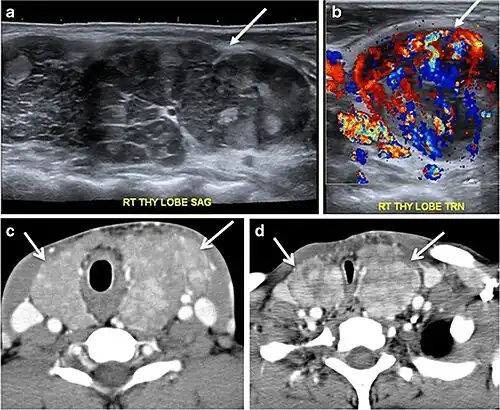

Fig. 14. A 19-year-old male patient known to have multi-nodular goiter and FNA, showing underlying Hashimoto's thyroiditis. a, b Sagittal and transverse greyscale and colour Doppler ultrasound of the neck demonstrate a hypoechoic enlarged right thyroid lobe with small hyperechoic regenerative nodules and marked hypervascularity (white arrows). c, d Enhanced axial CT scan images of the neck demonstrate a heterogeneously enhancing and enlarged thyroid gland, left more than right lobe, and the trachea is markedly narrowed.[1] -